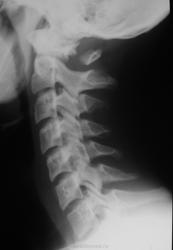

Уважаемые коллеги, не могу определиться с патологией остистого отростка С1. Подросток 16 лет, травму отрицает. Поступил на плановое обследование в неврологическое отделение. Жалобы типичные для ВСД. Есть сведения о натальной травме ШОП.

Первый шейный позвонок остистого отростка не имеет ( см.Коваль Г.Ю.). К сожалению, качество изображения не позволяет судить об остальном.С уважением. Ильич.

Незаращение задней дуги С1.

Что-то по типу отсутствия оссификации задней дуги атланта.. Ничего похожего в литературе не встречала..

Спасибо за комментарий, но остистый отросток С1 виден, только отдельно лежащим костным фрагментом. За качество извиняюсь, но цифры у нас нет.

Спасибо, случай очень интересный. Мне такое не встречалось. На втором снимке еще и конкресценция С2-С3.

То, что в обоих случаях выглядит отдельным костным фрагментом, это скорее задний бугорок атланта и прилежащие к нему части дужек. Остистого отростка у С1 нет в принципе.

Spina bifida C1 с гиперплазированным задним бугорком.

Я бы написала двусторонее незаращение задней дуги атланта.

Кроме сказанного, имеет место и наклон ("кивок") задней дуги C1 кпереди.

Всем спасибо за комментарии. Прямой снимок сделали, но никаких видимых отклонений от нормальной картины не отмечается, а качество не позволяет выставить на сайте. Всё же хочется узнать причину видимой картины - врождённая аномалия или последствие натальной травмы позвонка?

Безусловно, врожденное состояние.

Согласна с врожденным двусторонним несращением задней дуги с боковыми массами у С1.